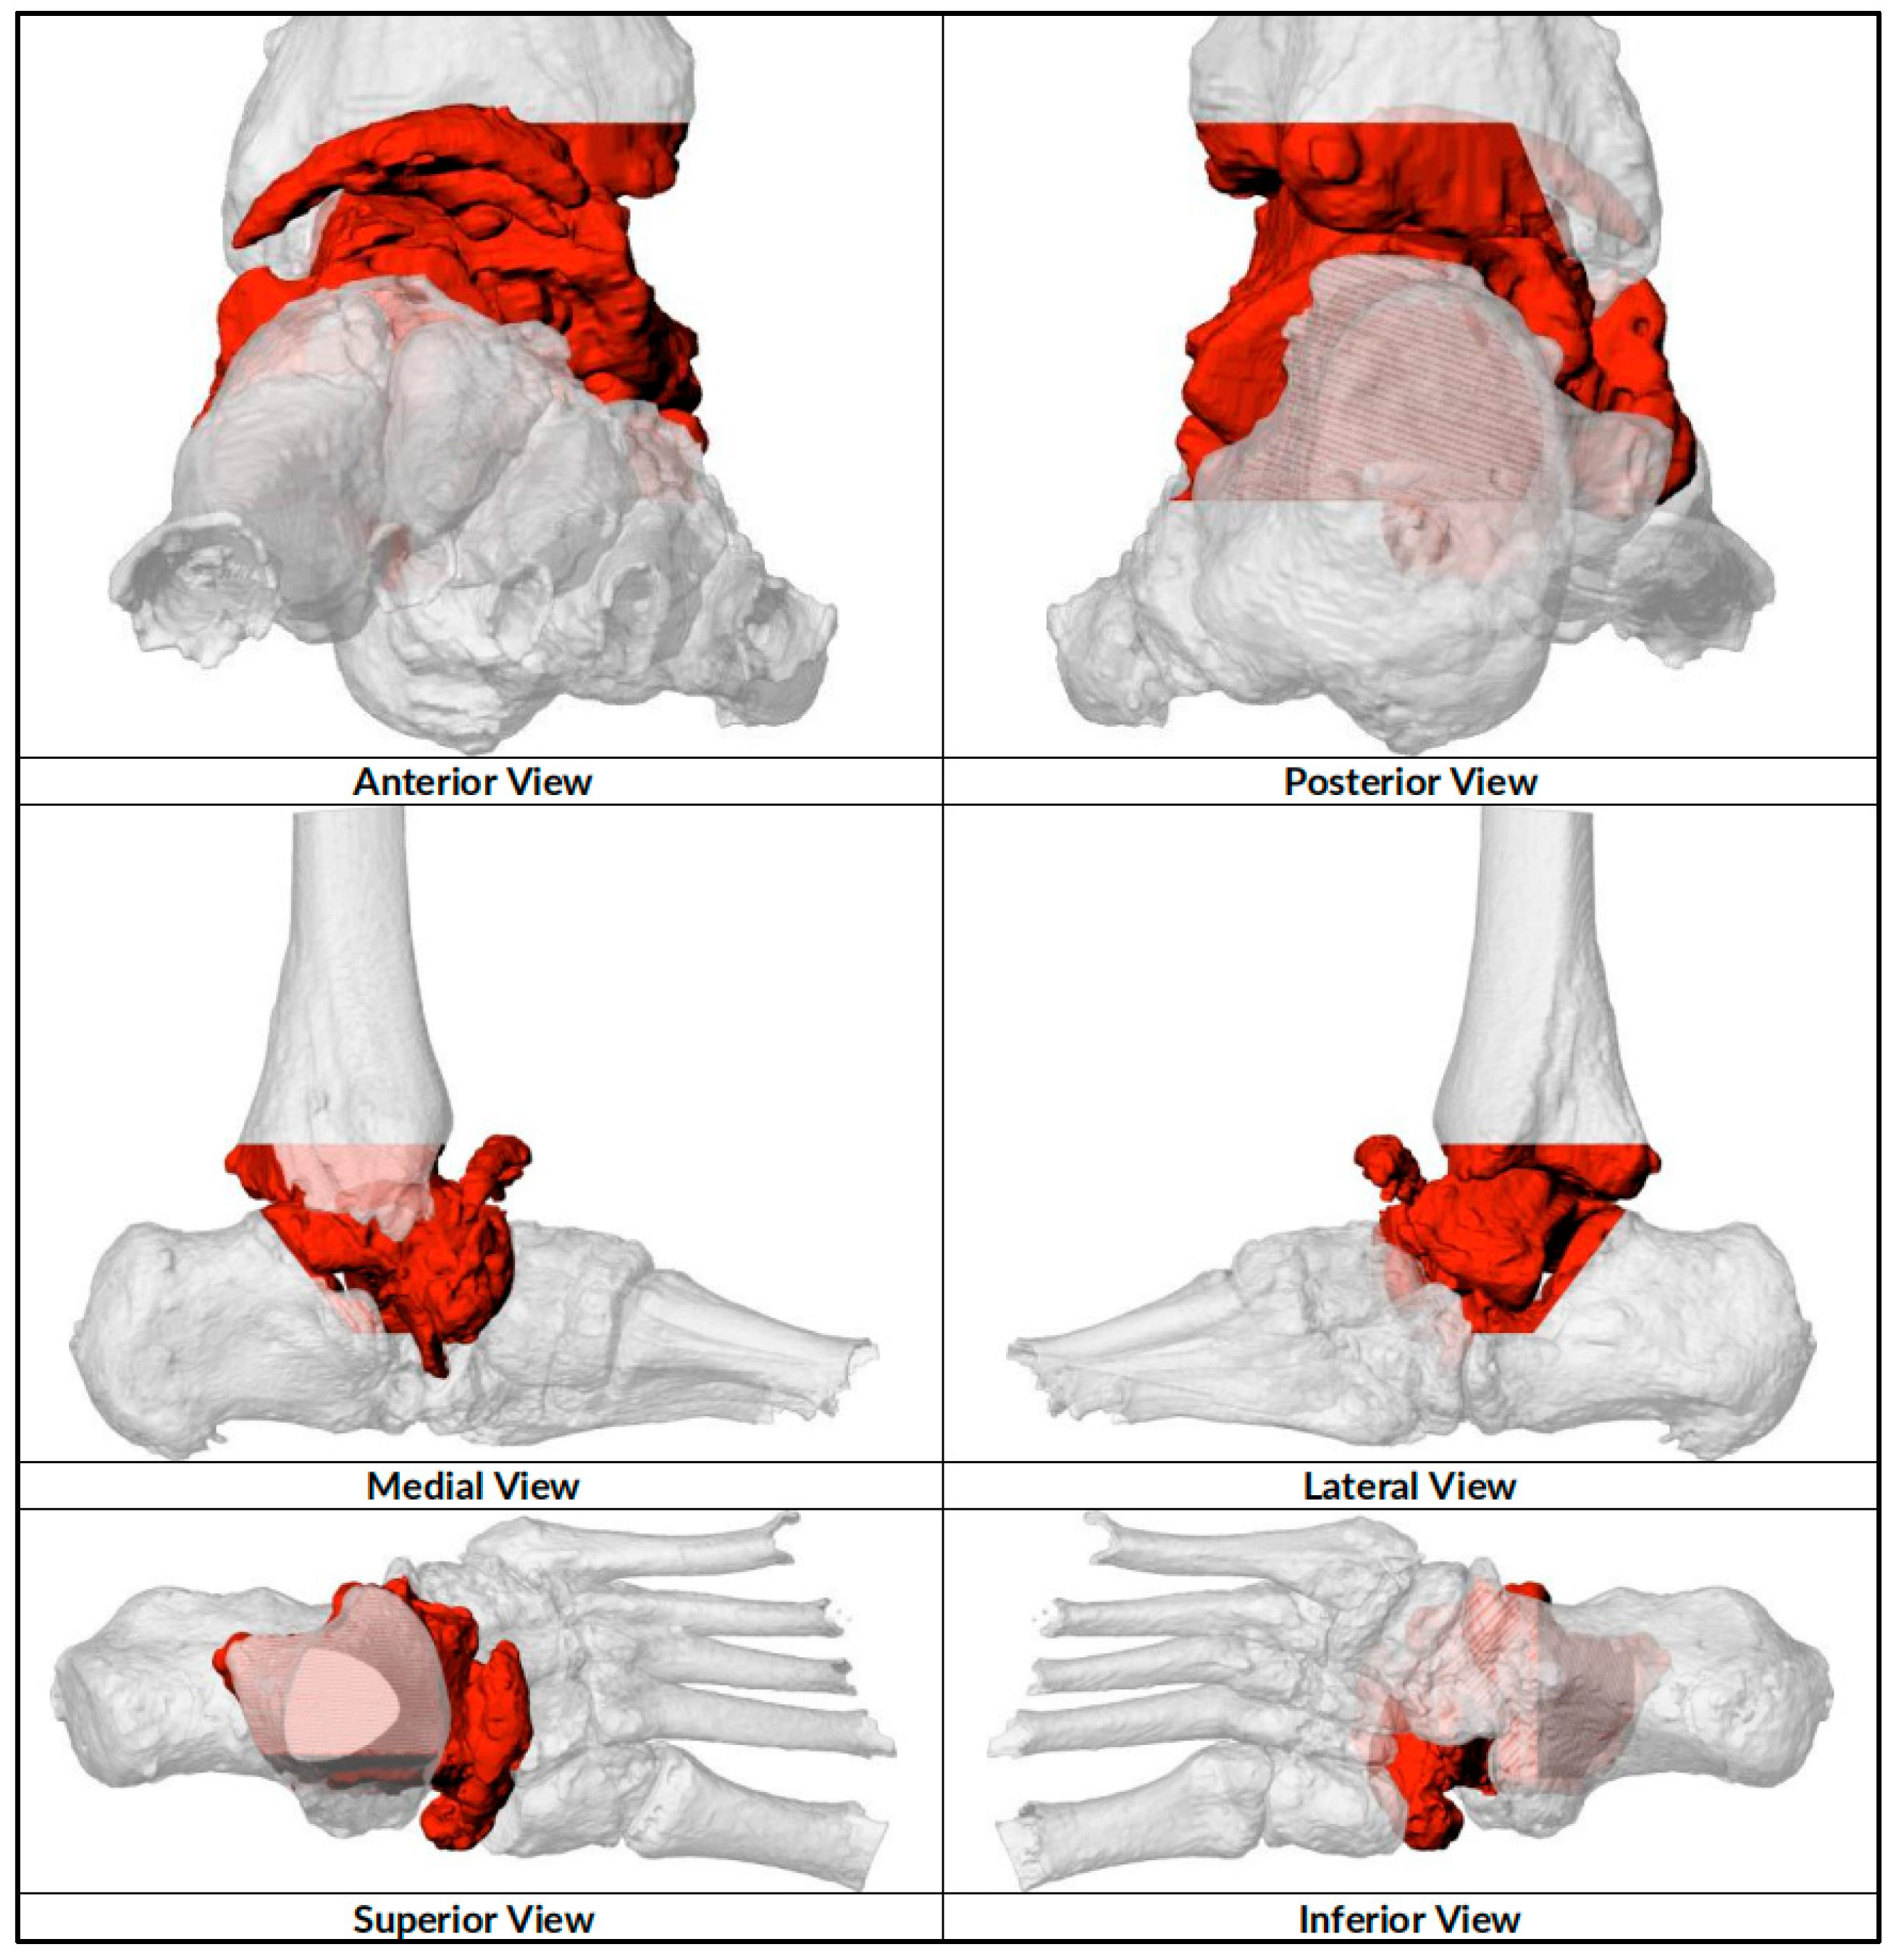

2.1. Preoperative Planning

2.2. Surgical Technique